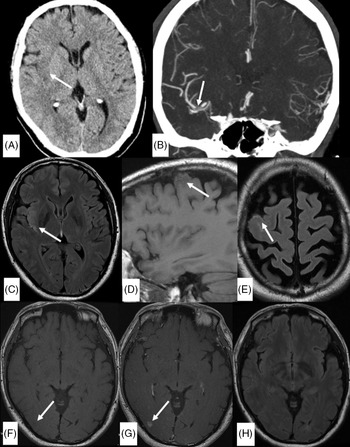

A 53-year-old man who underwent recent mitral valve repair and tricuspid valve annuloplasty 3 months prior presented with transient mild left-sided facial droop and dysarthria. He had a National Institute of Health Stroke Scale (NIHSS) of 1. Initial unenhanced CT and CT angiogram (Figure 1A and B) demonstrated acute infarct in the right insula secondary to a filling defect in right distal middle cerebral artery (MCA). MRI vessel wall imaging was performed 12 h after initial CT to clarify the etiology of this filling defect and was concluded an embolus as there was no evidence of wall thickening or enhancement. Limited brain sequences (Figures 1C–H) performed concurrently demonstrated high fluid-attenuated inversion recovery (FLAIR) signal in the right insula, compatible with the infarct. There was additionally unexpected sulcal T1 and FLAIR hyperintensity overlying right frontal convexity and an area of contrast blush in the right occipital lobe without other corresponding abnormality allowing for lack of diffusion weighted imaging (DWI) and blood-sensitive sequences on this first MRI. While awaiting cardiac investigations, the patient developed visual field defect, prompting the second MRI brain with contrast (Figure 2). This MRI demonstrated a parenchymal hematoma in the right occipital lobe, with a focal area of enhancement centrally. The sulcal T1 and FLAIR hyperintensity were confirmed as blood products on the susceptibility weighted imaging (SWI) sequence, and there was restricted diffusion in the right insula, confirming the right MCA infarct. A subsequent transesophageal echocardiography demonstrated vegetation in the heart valves and he was commenced on moxifloxacin and doxycycline for 6 weeks. A digital subtraction angiography (DSA) was performed to exclude a mycotic aneurysm causing the parenchymal hematoma with this knowledge and was negative. He remained well without progression or development of new focal neurological deficit and was discharged with an NIHSS score of 0, 12 days after initial presentation.

Figure 1: Unenhanced axial CT head (A), coronal CT angiogram in the arterial phase (B,) and initial limited MRI examination (C–H). A: Right insular hypoattenuation (arrow in A) secondary to an occlusion in the M1 segment of right MCA (arrow in B). (C) Axial FLAIR sequence demonstrate high signal in the right insula (arrow) corresponding to hypoattenuation on unenhanced CT. (D and E) Pre-gadolinium sagittal T1 FLAIR sequence and axial FLAIR sequence demonstrate intermediate T1-weighted signal and high FLAIR signal in the sulci overlying the right frontal convexity (arrows). (F and G) Pre- and post-gadolinium T1 FLAIR sequence (for vessel wall imaging) shows unexpected contrast blush in the right occipital lobe (arrow in G) in an area of probable T1 hypointensity (arrow in F). (H) Axial FLAIR sequence at the level of the right occipital lobe did not show corresponding abnormality. *A DWI or SWI sequence was not routinely performed with the vessel wall imaging protocol in our institution.